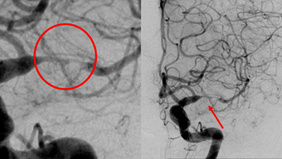

From Invisible to Curable Endovascular Cure of a Heubner’s Micro-AVM in a Child

By Nguyen Ngoc Minh LE

Published on December 11, 2025